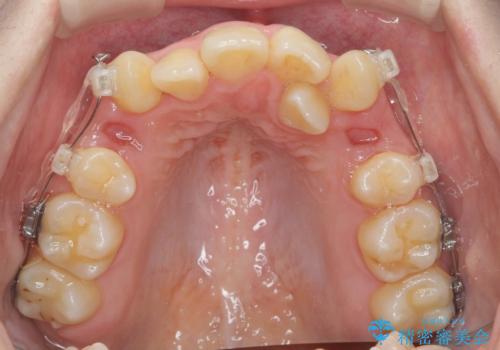

歯並びのせいで歯ブラシがしづらい マルチブラケットを用いた抜歯矯正

- 歯並びのがたつきにより歯ブラシがしづらく、今後虫歯になってしまう不安から、矯正治療を希望されて来院されました。

歯を並べるにはスペースが不足しているため、小臼歯の抜歯を4本行うマルチブラケット矯正による治療を計画します。

治療後は非常に歯ブラシがしやすくなったと、治療結果に満足いただくことができました。